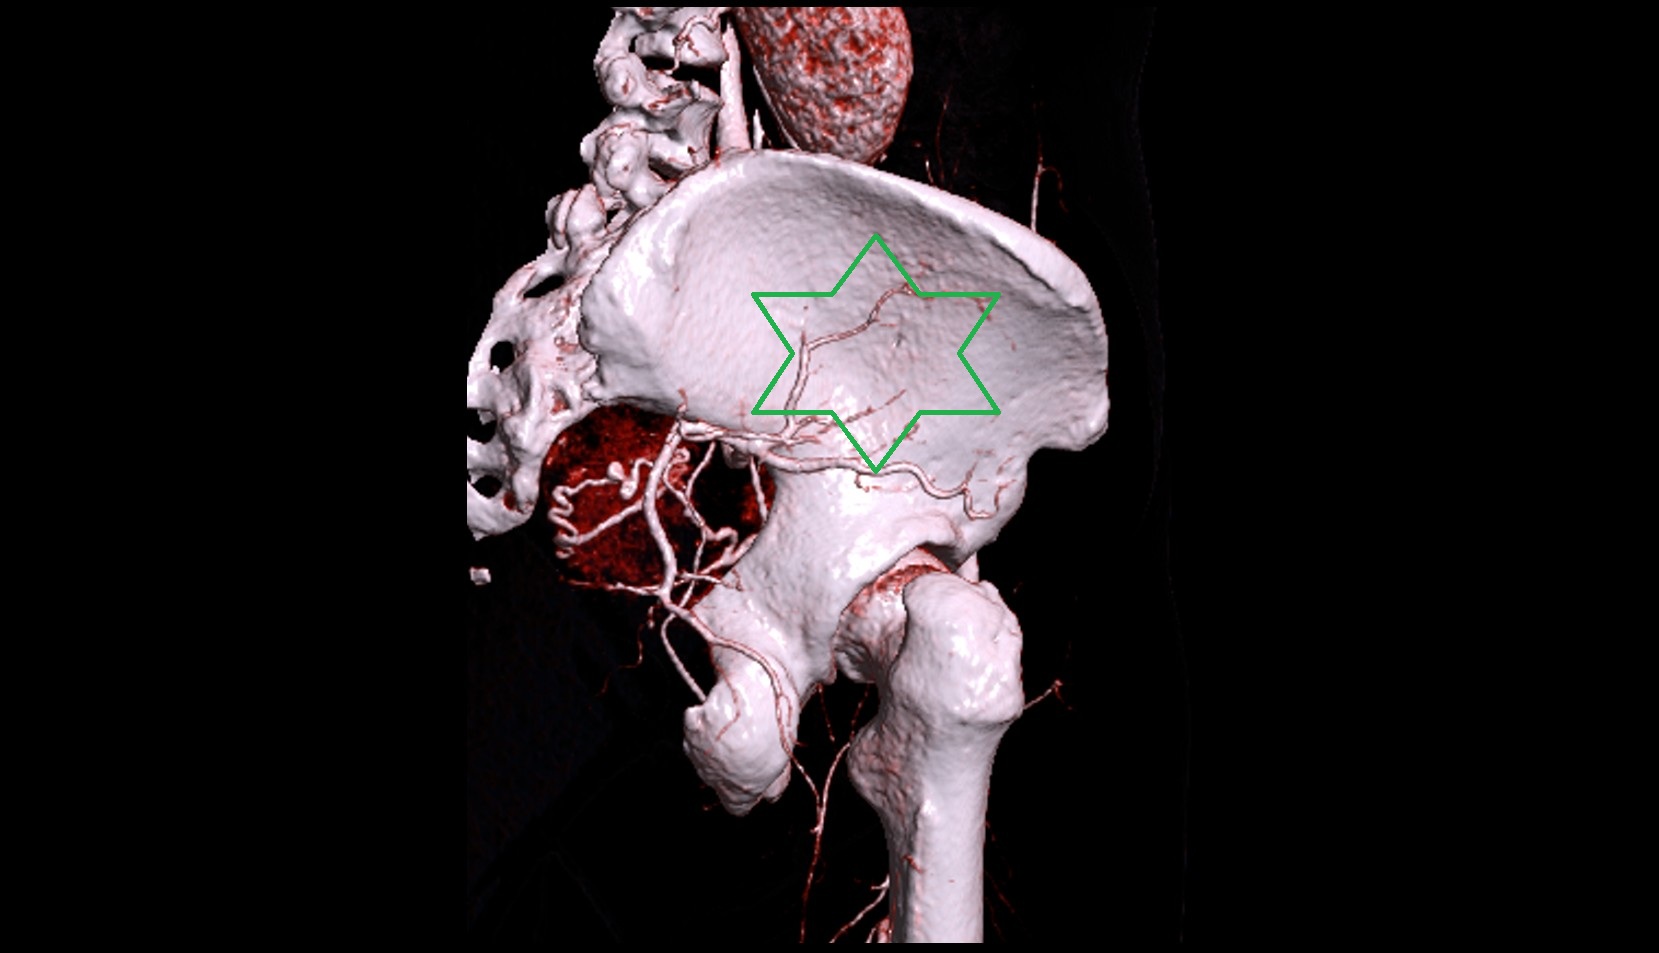

- Ala of ilium (wing of ilium)

- Iliac crest

- Acetabulum

- Ilium bone

- External iliac artery

- Internal iliac artery

- common iliac artery

- Aortic bifurcation